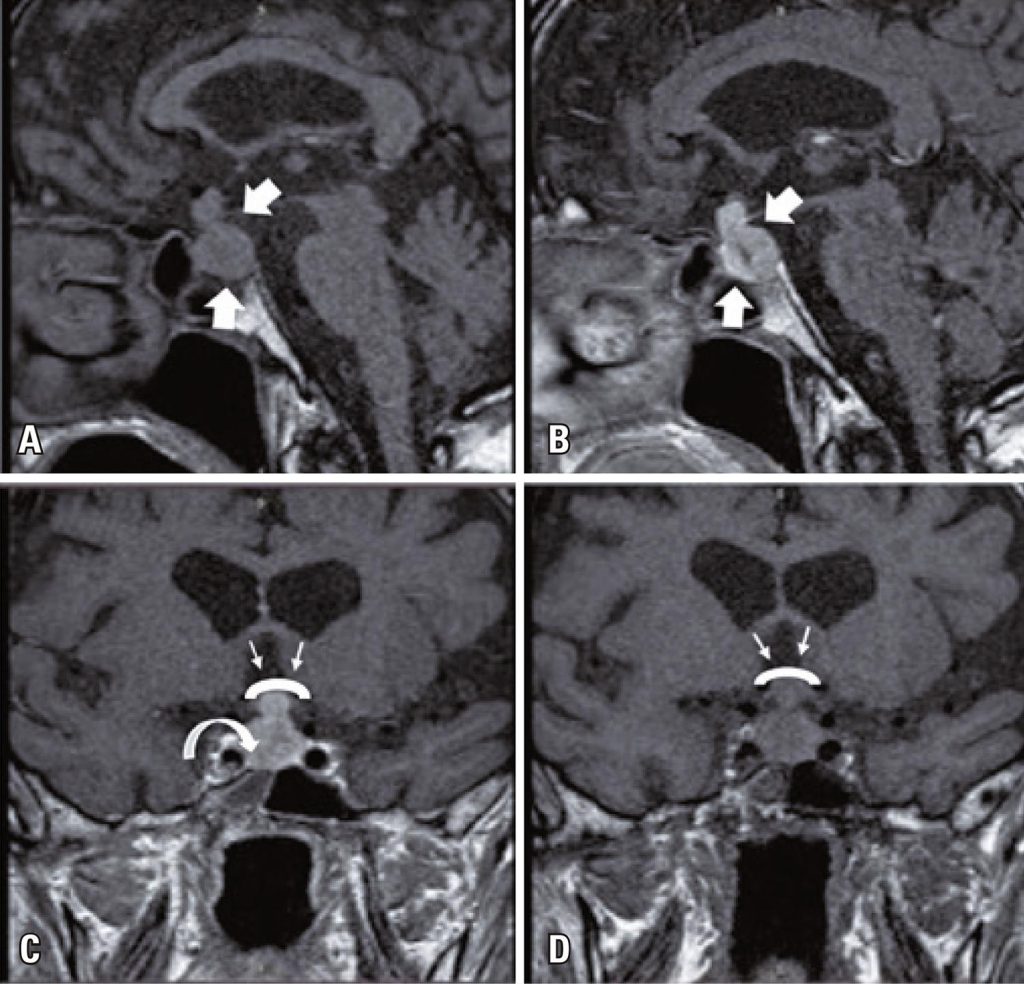

In this article, we present a case of diffuse follicular variant papillary thyroid carcinoma with pituitary metastasis, which is a rare cause of pituitary metastasis. The follicular variant of papillary thyroid carcinoma is an uncommon variant of papillary carcinoma. A 74-year-old male was presented with weakness, fatigue, and a decreased appetite. The patient was diagnosed with secondary adrenal and thyroid insufficiencies. Imaging revealed a pituitary mass with suprasellar extension, right cavernous sinus invasion, and optic chiasm compression. Thyroid ultrasonography revealed a nodule with a maximum size of 7.2cm in the right lobe. Cytological examination via fine-needle aspiration suggested papillary thyroid cancer. Total thyroidectomy with central and right lateral neck dissection confirmed the diagnosis of diffuse follicular variant of papillary thyroid carcinoma. Owing to visual field defects, the patient underwent transsphenoidal surgery. Histological and immunohistochemical evaluations confirmed pituitary metastasis from the papillary thyroid cancer. Radioactive iodine treatment and gamma knife radiotherapy of the pituitary gland were performed. The initiation of sorafenib treatment was deemed appropriate during the follow-up. A significant decrease in the thyroglobulin levels was observed after sorafenib treatment. Pituitary metastasis should be considered in patients diagnosed with hypopituitarism and pituitary lesions at initial evaluation. The presence of visual field defects may be an indication for neurosurgical intervention and guide both diagnosis and treatment. The management of papillary thyroid cancer and the role of treatment modalities in prognosis depend on the biological behavior of the tumor. Early diagnosis and multidisciplinary management are crucial for the treatment of these patients.